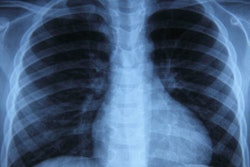

Researchers from Stanford University have released a massive dataset of more than 224,000 chest x-rays to be used for the development of artificial intelligence (AI) algorithms. The group has also launched a competition for developers of AI algorithms to test their models.

Called CheXpert, the database was released by Stanford's Machine Learning Group. It features 224,316 chest radiographs and radiology reports retrospectively gathered on 65,240 patients at Stanford Hospital's outpatient and inpatient centers between October 2002 and 2017.

Importantly, each radiology report is labeled as positive, negative, or uncertain for the presence of 14 specific observations. These structured labels were created for the images by an automated rule-based labeler developed by Stanford that uses natural language processing to extract observations from free-text radiology reports. This open-source automated labeler is also publicly available for download.